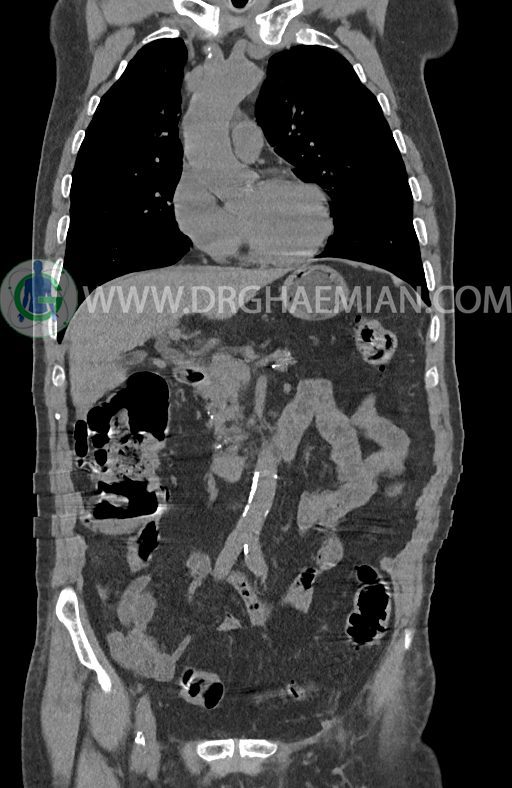

در سی تی اسکن اسپیرال ریه ها و مدیاستن، شکم و لگن با و بدون کنتراست وریدی (مولتی دیدکتور 16 با مقاطع ظریف و بازسازی کرونال) :

–افزایش ضخامت تومورال دیستال مری و GEJ در سگمانی به طول 4cm-5cm (T2 or T3)

–آتروفی نسبی پانکراس همراه با فوکوس های کلسیفیه ی منتشر پارانشیم مطرح کننده ی پانکراتیت مزمن

-CBD بسیار دیلاته (16mm) همراه با دیلاتاسیون مجاری داخل کبدی سنترال بدون شواهد سنگ یا توده در مسیر

–کیست های کورتیکال متعدد هر دو کلیه به بزرگترین قطر 56mm

نتیجه : T(2or3)/N2/M0